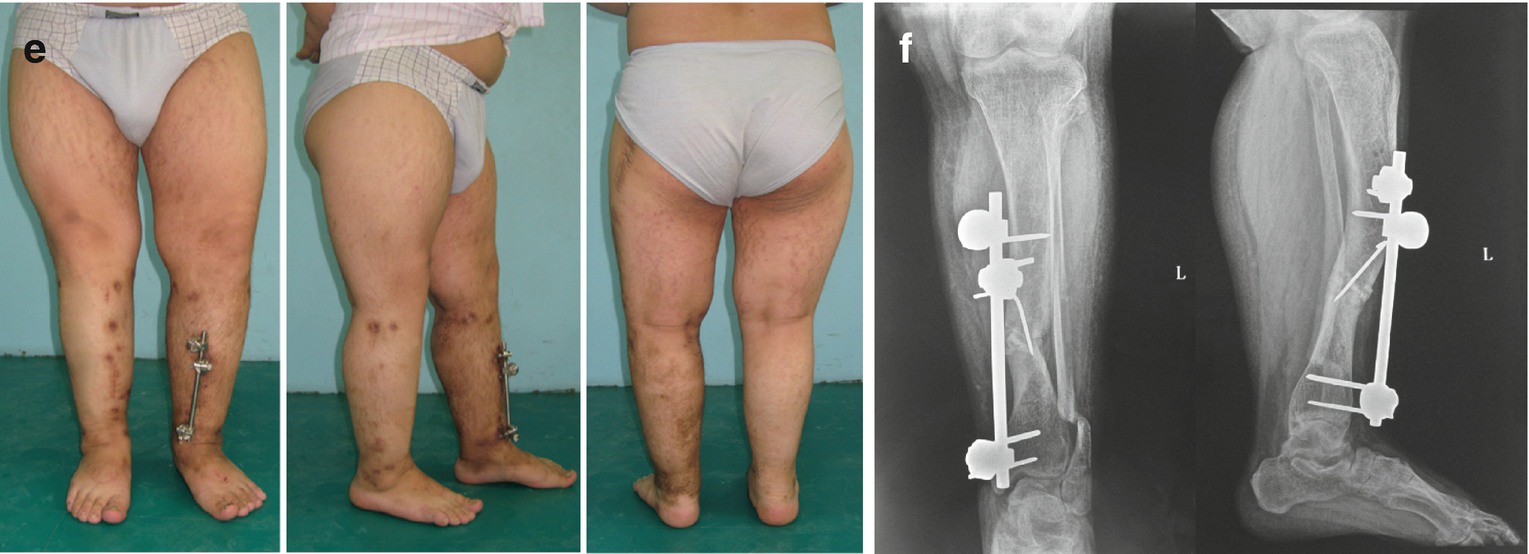

Traumatic Sequelae Of Lower Limb Springerlink

Lower Limb Deformity Caused By Hereditary And Metabolic Diseases Springerlink